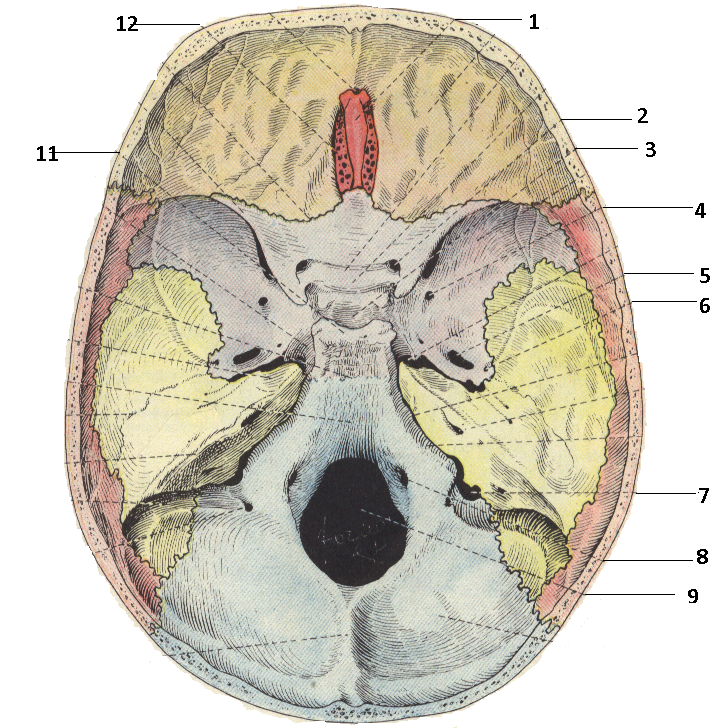

Анатомические детали: Фотографии топографии черепа с нижнего вида